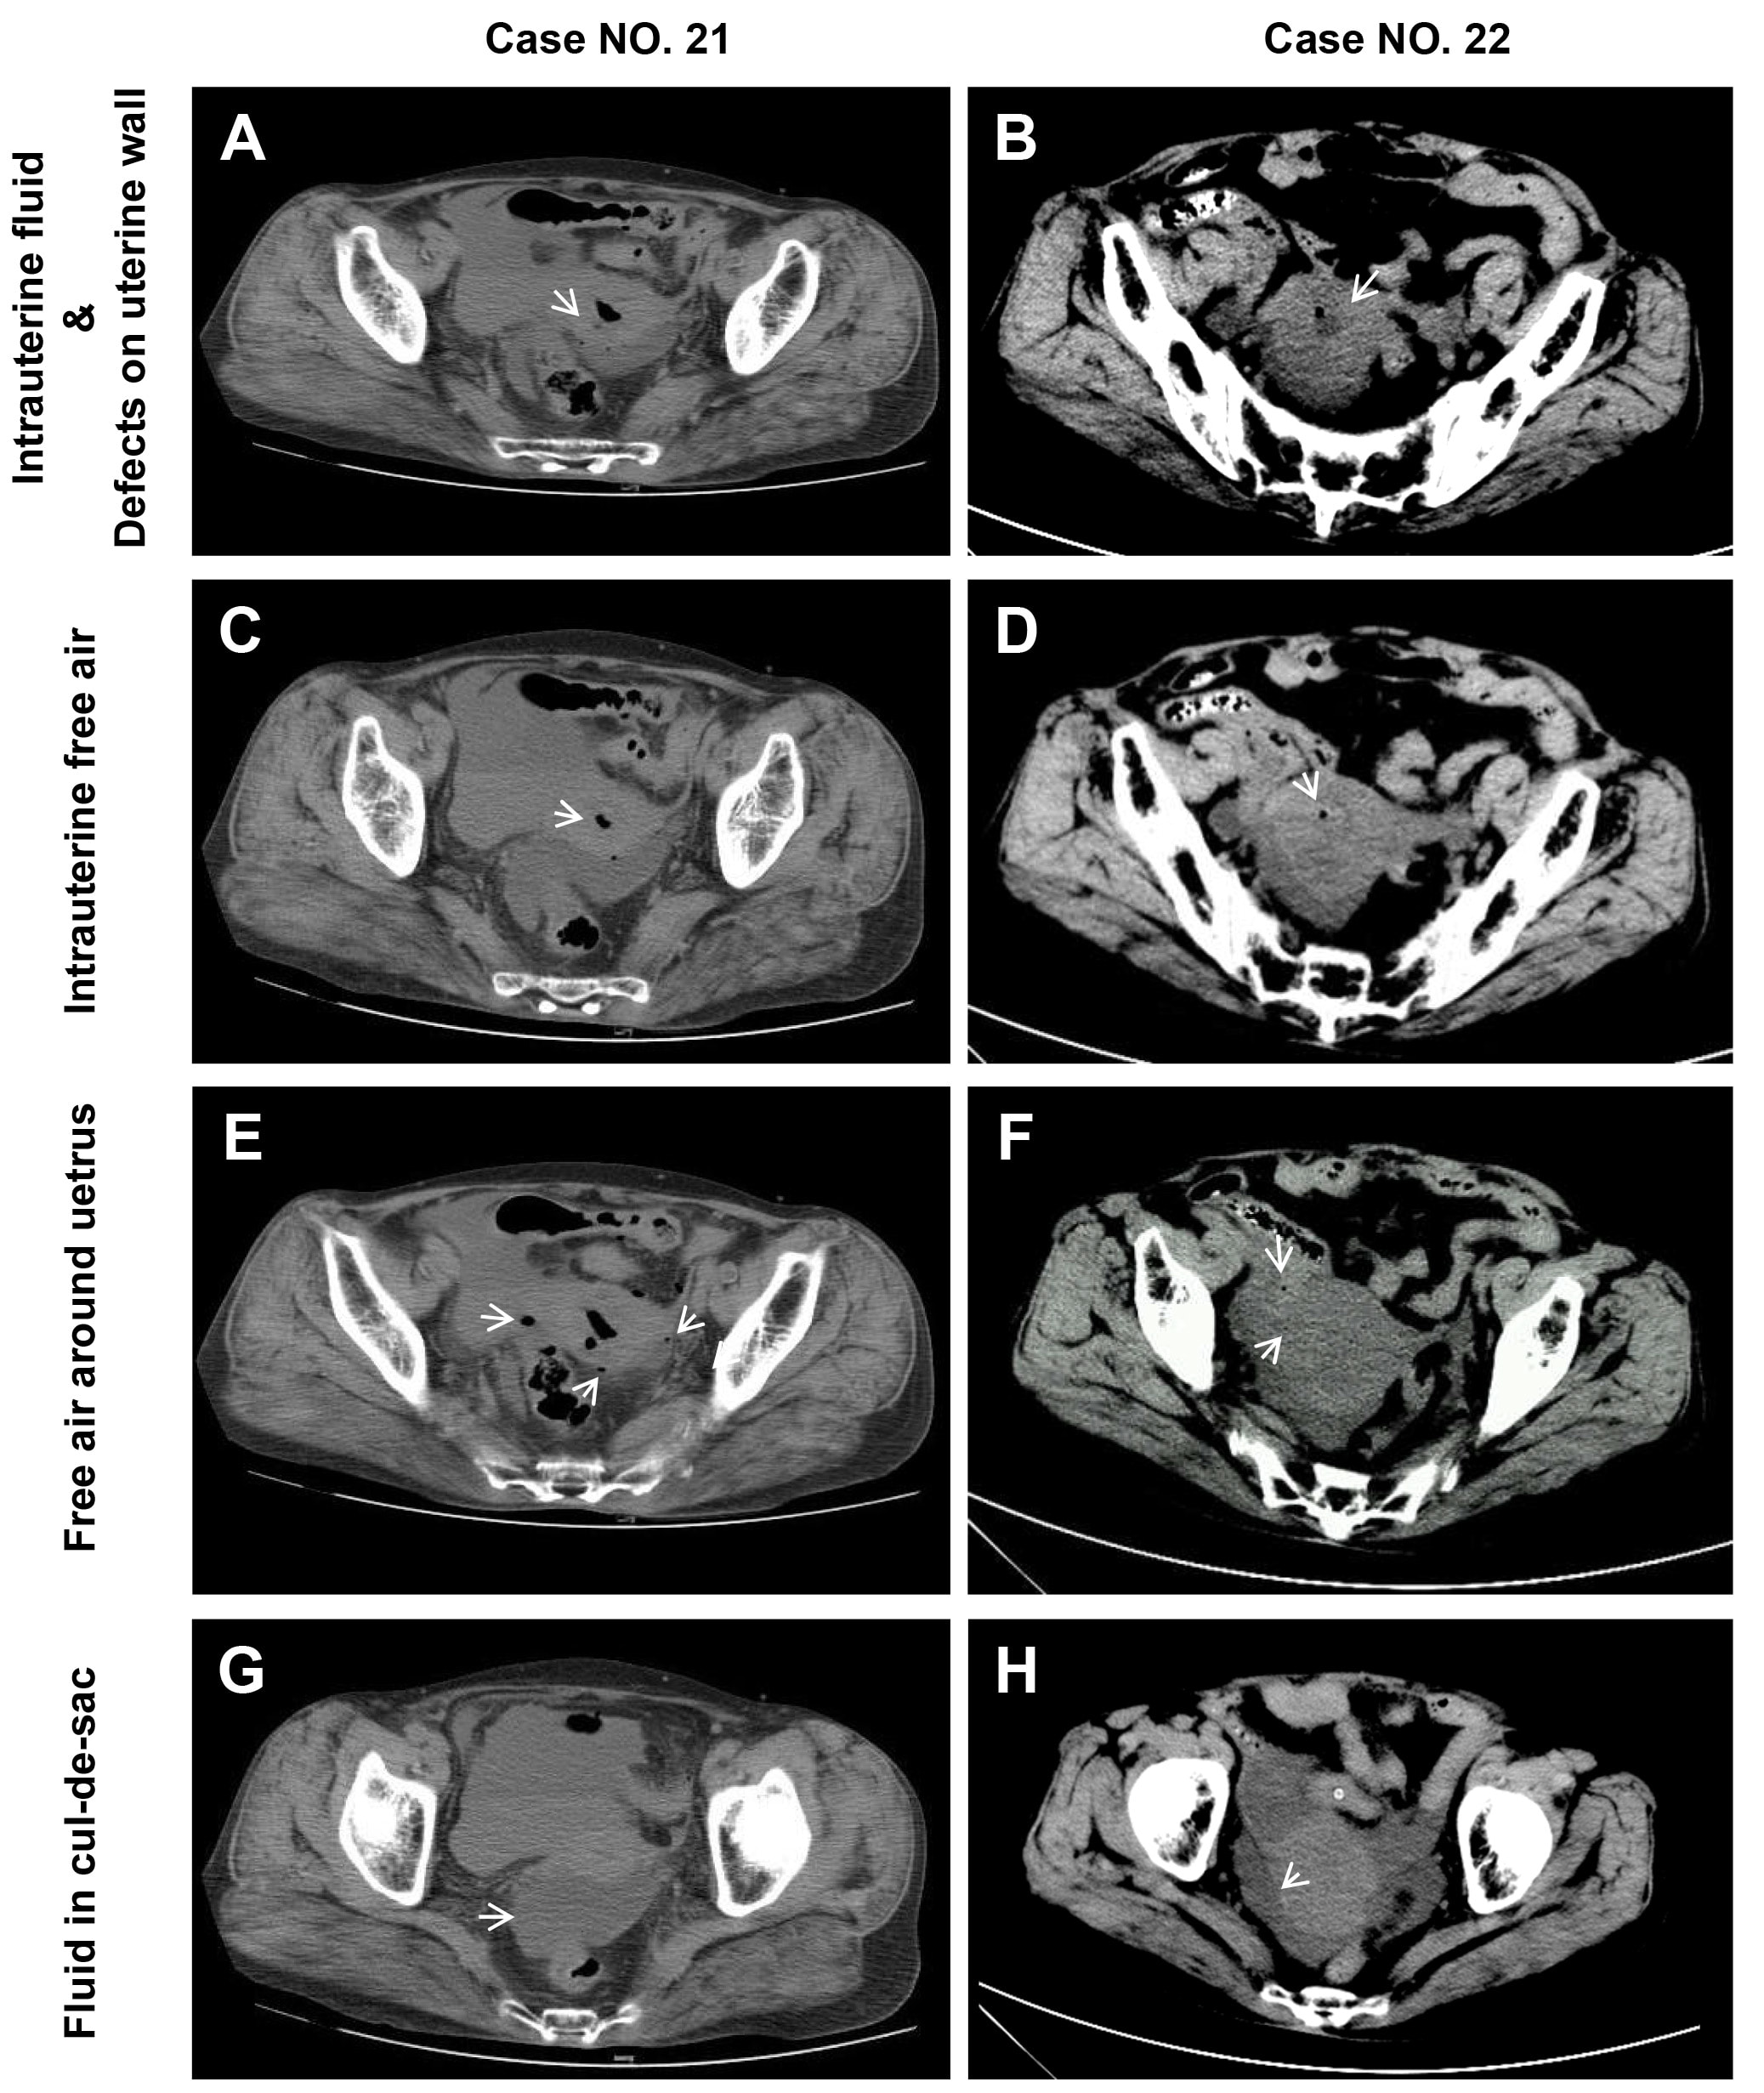

Fig. 2.Representative CT images of 5 featured signs in spontaneous perforation of pyometra. This figure presents CT images of two cases from the authors’ hospital. The five representative CT features for spontaneous perforation women are listed. These are “Intrauterine fluid” & “defects on uterine wall” (arrow, A,B), “Intra-uterine free air” (arrow, C,D), “free air around uterus” (arrow, E,F), “fluid in cul-de-sac” (arrow, G,H).

Five CT signs were frequently observed in uterine perforation patients, while none of them could been detected in GI perforation cases. These were uterine fluid (22 patients, 100%, Fig. 1, Fig. 2A,B), intrauterine free air (20 patients, 90.1%, Fig. 1, Fig. 2C,D), free air around the uterus (17 patients, 77.3%, Fig. 1, Fig. 2E,F), defect in the uterine wall (16 patients, 72.7%, Fig. 1, Fig. 2A,B), fluid collected in the cul-de-sac (21 patients, 95.5%, Fig. 1, Fig. 2G,H). After thorough examination of the GI perforation CT images, only very few of the above five signs were noted (Fig. 1).